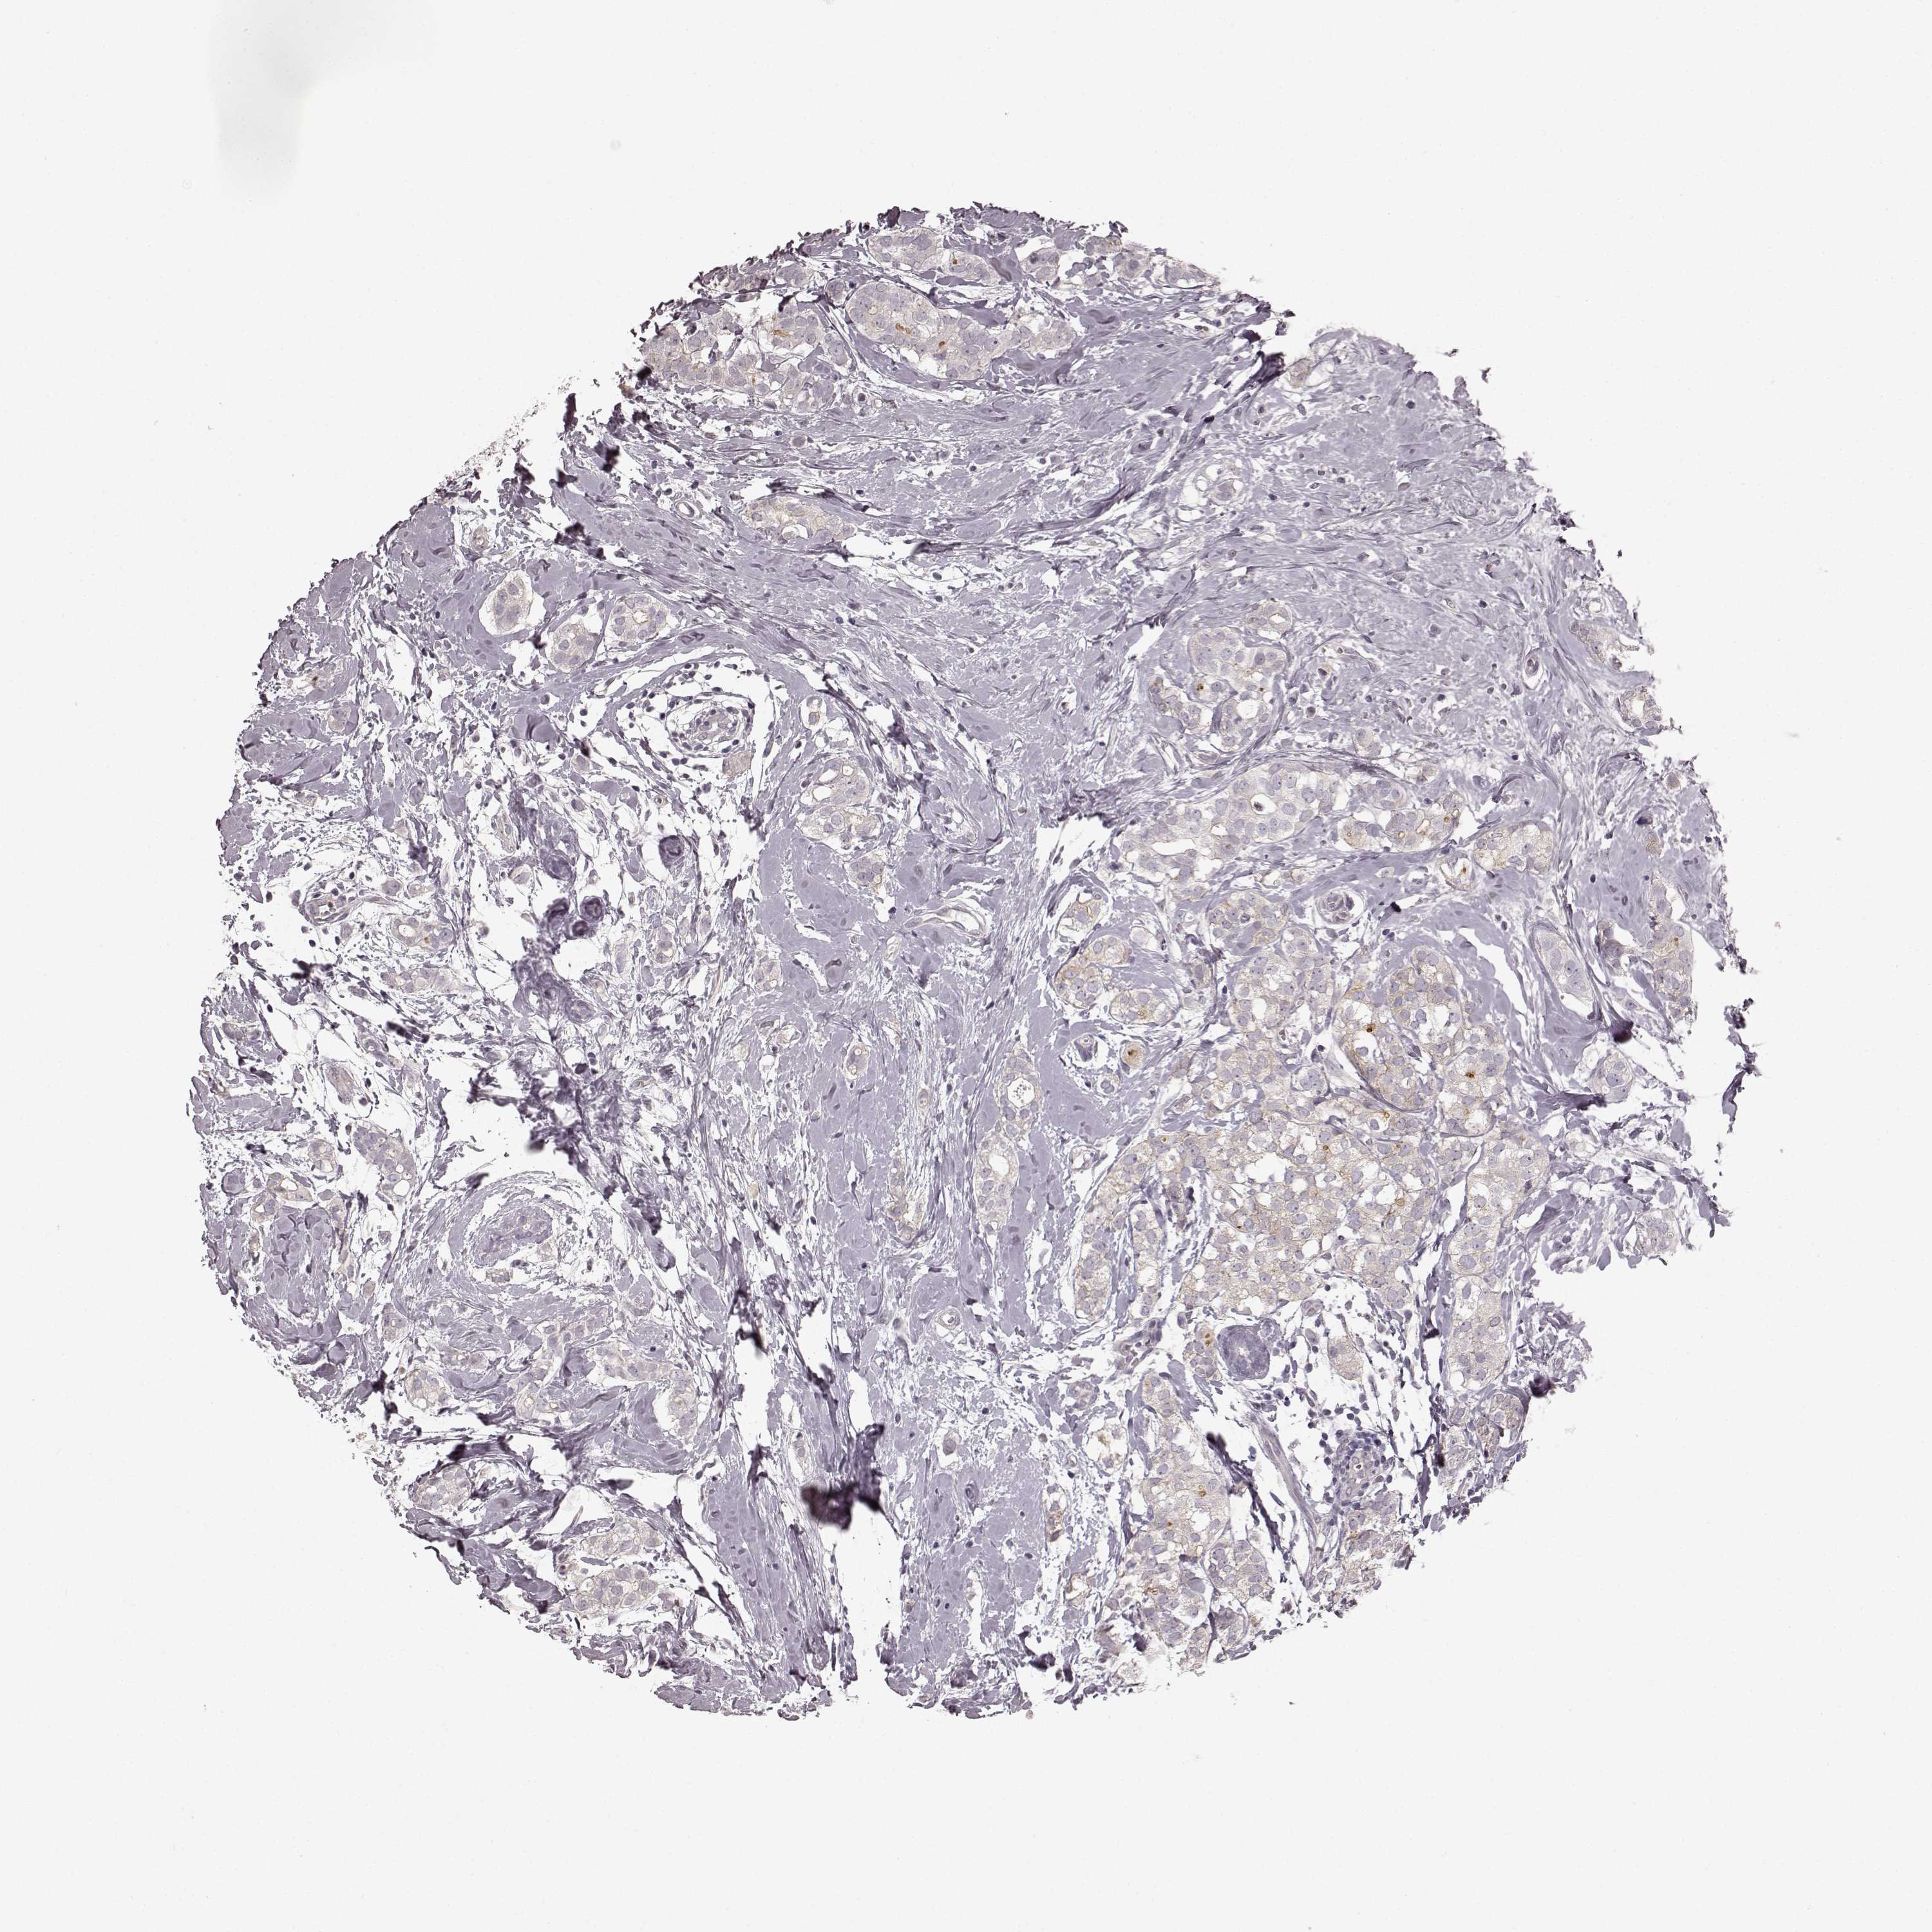

CANCER BREAST CANCER Show tissue menu

BRCA TCGA BRCA VALIDATION PROTEIN EXPRESSION